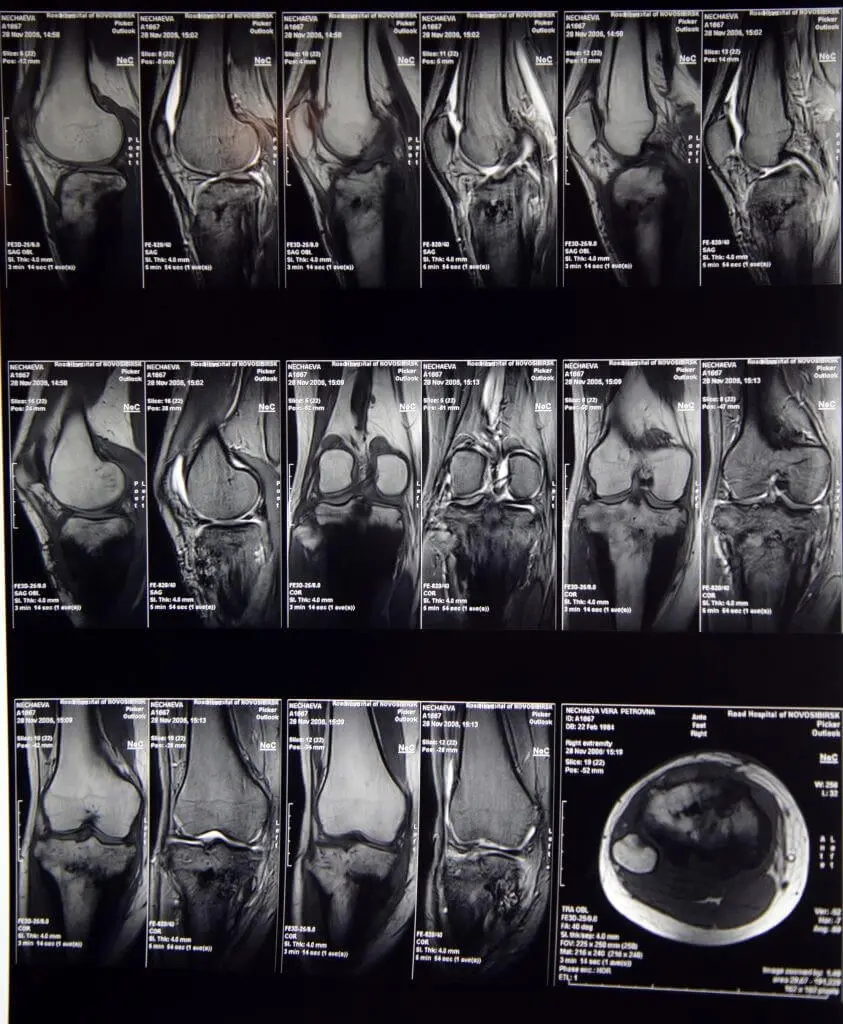

МРТ коліна дозволяє бачити тонкощі і особливості ушкодження тканини коліна, наприклад при травмі (меніски, зв’язки, скриті переломи кісток і багато іншого).

МРТ колінного суглоба (фото 1)

МРТ суглобів, читати більше.

Виявлена на МРТ травма меніска не завжди потребує термінової операції (артроскопія або традиційна хірургія). Багаторічна статистика відділу МРТ Центру «Меддіагнстіка» показала, що у 8 пацієнтів з 10 виявлено розшарування заднього рогу меніска. При цьому болі в коліні не було і функція коліна не було порушено. Такі пацієнти не вимагали хірургічного втручання.